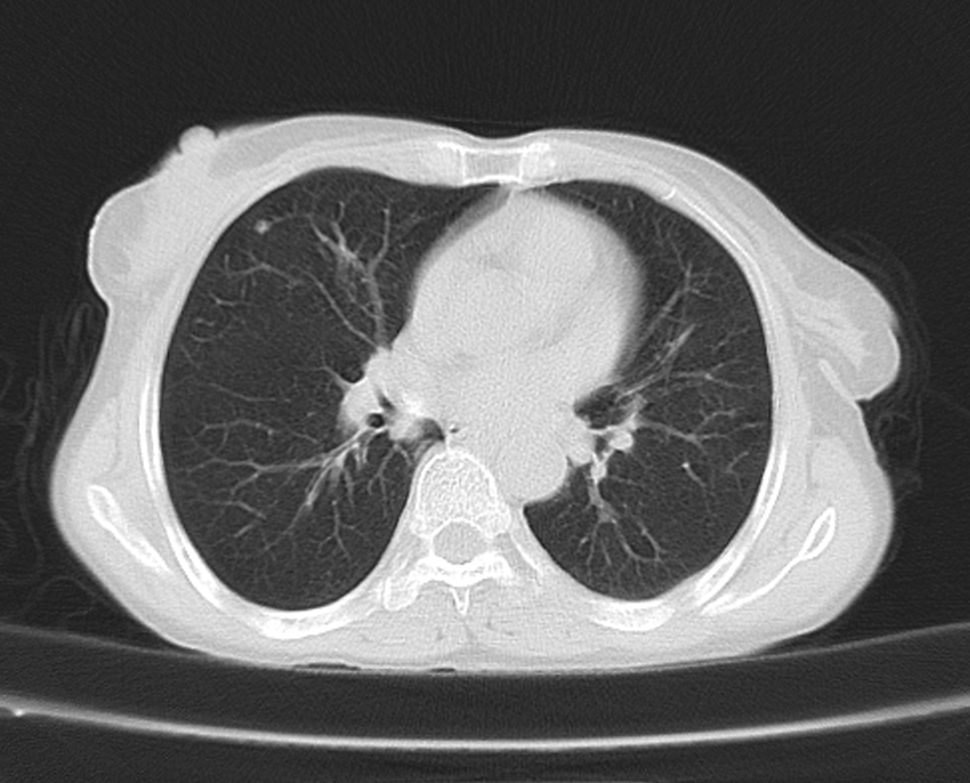

标题: CT21609:右乳包块1年,请各位讨论分析一下,乳腺CA, [打印本页]

标题: CT21609:右乳包块1年,请各位讨论分析一下,乳腺CA,

考虑---右乳癌并胸壁、肋骨、双肺转移。

考虑乳腺癌侵犯肋骨、胸壁及两肺转移可能性大。

右乳癌并胸壁、肋骨、双肺转移。

考虑右侧乳腺癌侵犯肋骨、胸壁及两肺转移。

支持考虑---右乳癌并胸壁、肋骨、双肺转移。

考虑右侧乳腺癌侵犯肋骨、胸壁及两肺转移可能。

考虑右侧乳癌并胸壁、肋骨及双肺多发性转移。